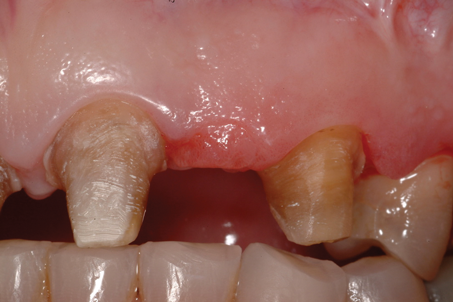

A patient presented with two defective 3-unit fixed partial dentures spanning teeth Nos. 6 through 8 and teeth Nos. 9 through 11 (Figure 7). The defective fixed partial dentures were removed (Figure 8), an impression was made, and traditional provisional fixed partial dentures without ovate pontics were placed. After the impression was sent to the laboratory, the lab technician prepared ovate pontic sites on the stone cast (Figure 9) and fabricated the new definitive bridges. On the day of insertion, the provisional fixed partial dentures were removed (Figure 10), ovate pontic sites were prepared using a teardrop-shaped diamond bur (Figure 11), and the sites were sounded to confirm that there was at least 2 mm from the base of the pontic site to the alveolar bone (Figure 12). The fixed partial dentures were cemented, and the postoperative healing was uneventful (Figure 13).

(8.) Retracted close-up view after removal of the defective fixed partial dentures.

Figure 8

(10.) Close-up view of the existing edentulous tooth No. 10 site prior to the creation of the ovate pontic site.

Figure 10